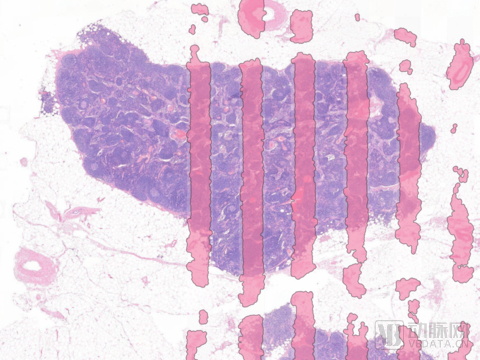

数字病理是一种基于图像的动态环境,能够采集、管理和解释从数字化切片生成的病理信息。通俗来讲,是指通过扫描技术对病理数据进行数字化采集(将传统病理的物理切片转换成高分辨率数字图像),医生通过数字化切片生成的信息进行病理诊断以及病理数据管理。数字病理是数字成像技术(又称计算机成像技术)在病理学领域的成功实践,包括临床和非临床两方面的应用。临床应用:包括通过数字病理图像进行日常病理学诊断以及开展远程病理诊断。非临床应用:包括科研和教学。

阅片环节:结合数字扫描技术,实现数字化阅片。传统病理阅片需要进行人工分片后,医生通过显微镜对物理切片进行分级审阅。传统的模式下,医生审片等待时间长,并且受限于实验室和显微镜。进行数字化升级后,通过数字扫描仪,实体切片以扫描图片的形式在电脑端呈现,并且通过信息化的系统实现实时的分配。一方面,病理医生不再需要依赖显微镜,工作地点或能散布至临床科室,加强与临床端的沟通与合作。另一方面,以系统取代人工分片,可以极大程度节约医生的工作时间,从而提高工作效率。

扫描模块核心是扫描仪的配备。扫描仪是将物理切片转化为数字切片的基础。扫描仪的质量决定了输出图片的压缩情况,直接影响显示成像的质量,是数字切片能否还原模拟实体切片的第一步。